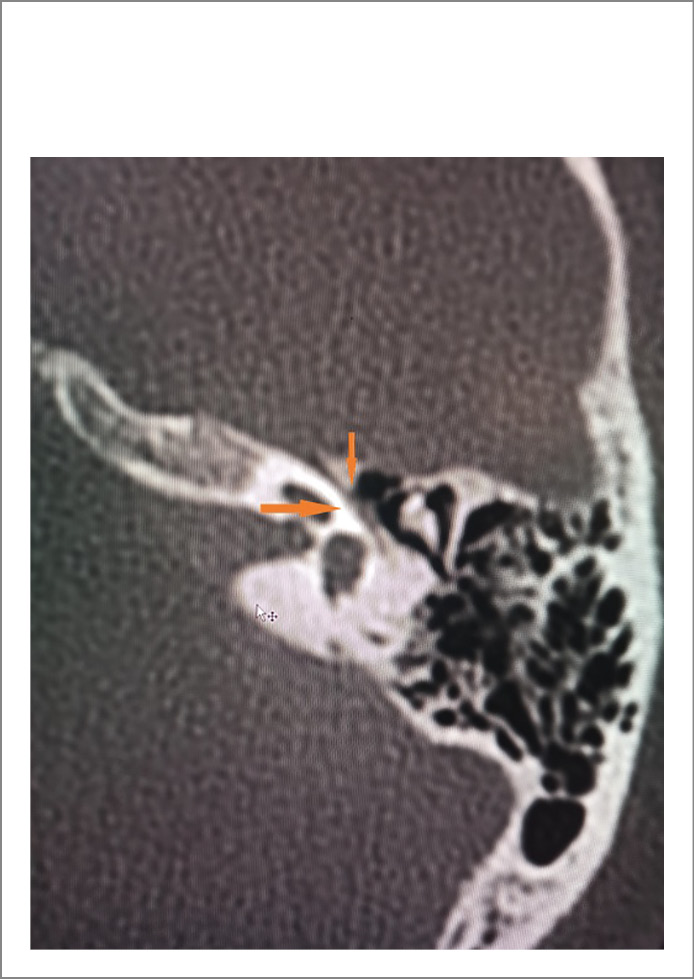

Лабораторно-инструментальные методы исследования: в клиническом и биохимическом анализах крови, общем анализе мочи отклонений от нормы не отмечено. По данным компьютерной томографии (КТ) височных костей патологических изменений в височных костях не выявлено (рис. 1). По данным КТ органов грудной клетки без патологических изменений очагового и/или инфильтративного характера в легких, верифицирован локальный участок пневмофиброза в верхней доле левого легкого; КТ-0. По результатам магнитно-резонансной томографии (МРТ) головного мозга обнаружены магнитно-резонансные признаки множественных очагов в белом веществе головного мозга (вероятнее всего, сосудистого характера), умеренного расширения субарахноидального пространства, низкое расположение миндалин мозжечка. Изменений в области мосто-мозжечкового угла не обнаружено (рис. 2, а, b). На магнитно-резонансной томографии черепных нервов с двух сторон визуализируется нормальный ход лицевых нервов (рис. 3). По данным ЭНМГ, выполненной на 5-е сутки от начала заболевания, определены признаки умеренно-выраженного поражения лицевого нерва слева. Характер поражения смешанный (поражение миелиновых оболочек и осевых цилиндров). Произвольная активация m. orbicularis oculi, m. orbicularis oris слева значительно снижена (рис. 4, а). Пациентка осмотрена оториноларингологом – данных за острую лор-патологию не выявлено, офтальмологом – OU «гипертоническая ангиопатия сетчатки».

Рис. 1. Лицевой нерв в лабиринтной части фаллопиева канала на КТ височных костей.